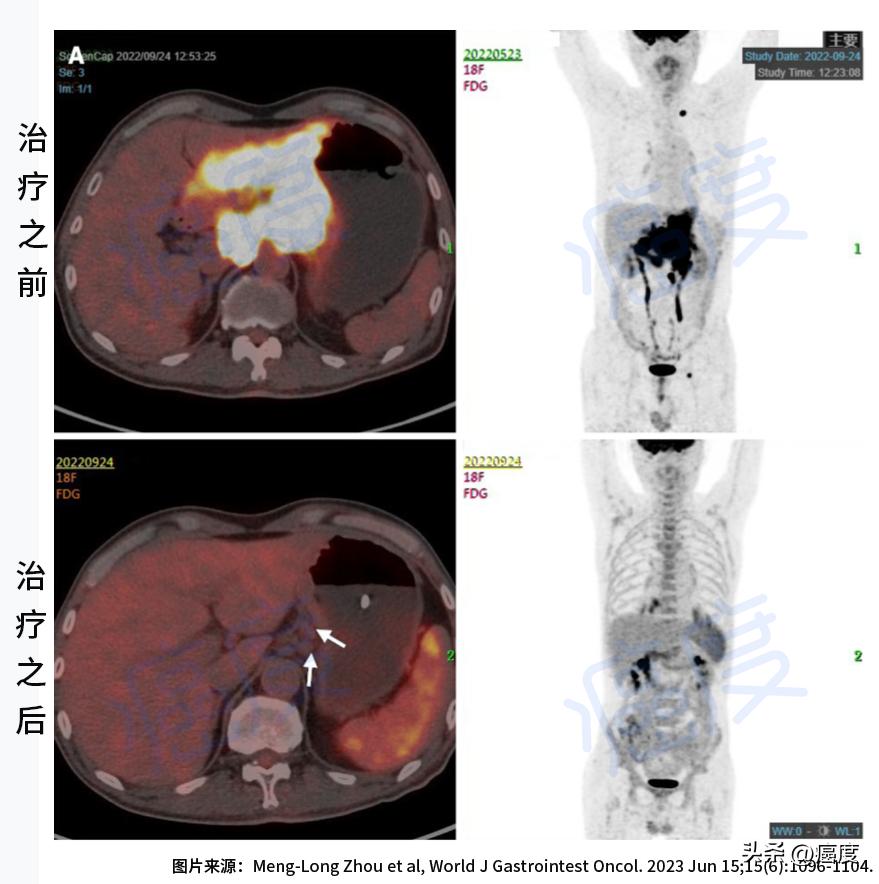

医生在给患者做检查的时候发现其脸色苍白,表现为贫血。左侧锁骨上区可触摸到肿大的淋巴结,但是腹部和直肠指检没看到异常的情况。肿瘤标志物都在正常的范围之内(肿瘤标志物不敏感)。但是胃部增强CT扫描可看到胃体壁增厚,胃周围、肝胃间隙、肺门区、腹膜后有肿大淋巴结,后面的PET-CT检查证实肿瘤已经转移。胃镜检查确定为胃癌。相应的分子检测指标是:微卫星稳定型、HER2两个+(弱阳性,但FISH验证为阴性),二代基因测序证实TMB的数值比较低,具体数值为5.98M/Mb。

治疗前后的影像学检查对比

治疗一个月之后,患者消化不良、黑便明显缓解,胃部增强CT扫描显示胃壁厚度减少,对示踪剂的吸收也降低,总体评估为部分缓解PR。

治疗之后病灶体积和示踪剂吸收明显减少